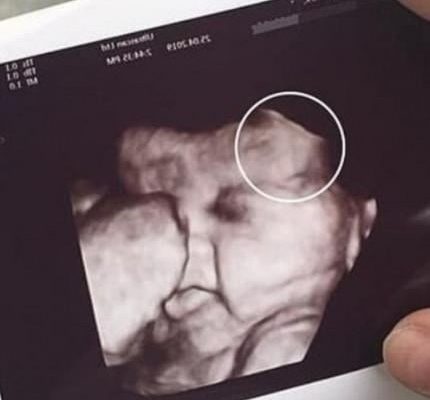

Doctors later explained that the initial scan had displayed an unexpected shape next to the developing baby, prompting the need for additional imaging. After a follow-up exam, they determined it was a benign artifact—a harmless visual distortion caused by the baby’s position and the machine’s angle. The clarification brought immense relief to both women, who had been preparing themselves for difficult news.

The family later expressed gratitude to the clinic for handling the situation with care and transparency. Medical specialists remind expecting parents that unusual ultrasound images are not uncommon and often resolve with clearer scans. The incident underscores the emotional weight of prenatal appointments and the importance of compassionate communication in moments of uncertainty.READ MORE BELOW